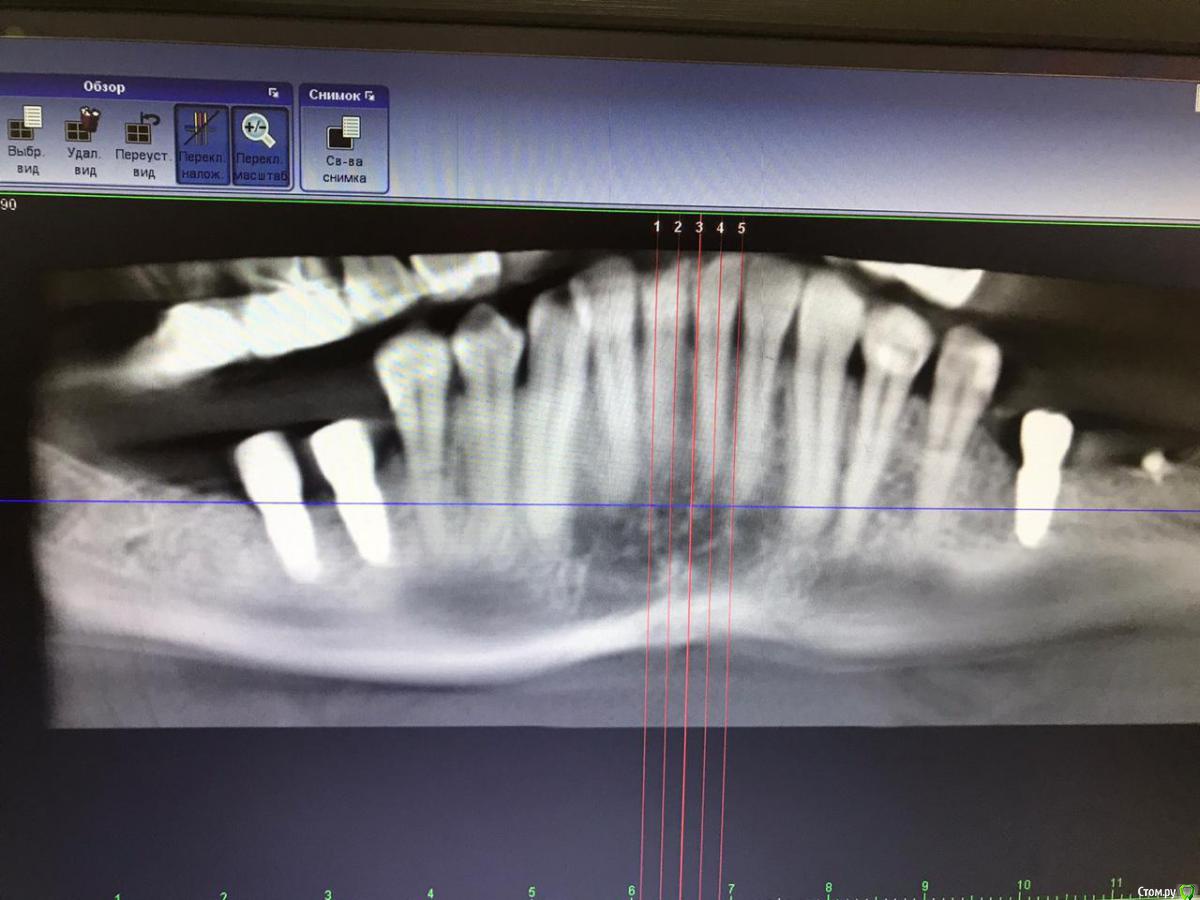

Виккиииии Опубликовано 25 марта, 2020 Поделиться Опубликовано 25 марта, 2020 2 имплантата 6,7 на них ставят коронки диоксид циркония что лучше 2 отдельные или одна слитная? была примерка после их срывали так что теперь все болит если они винтовые почему тогда так тяжело снимаются? Выглядят очень не естественно это норма для циркония? Ссылка на комментарий

Виккиииии Опубликовано 27 марта, 2020 Автор Поделиться Опубликовано 27 марта, 2020 в итоге это рулетка, повезло или нет.в итоге это рулетка, повезло или нет. установили коронки. Припухла щека, немного ноет, пью найм. Ставили с обеих сторон но болит только с одной где 6,7. Это нормально? Ссылка на комментарий

chervoncevdaniil Опубликовано 27 марта, 2020 Поделиться Опубликовано 27 марта, 2020 2 имплантата 6,7 на них ставят коронки диоксид циркония что лучше 2 отдельные или одна слитная На имплантах всегда лучше делать коронки соединенными,биомеханически и в плане обслуживания это лучше.Доказано клиническими исследованиями и наблюдениями,но если уже сделали разделенными то в принципе критичного ничего нет,но это было лишнее Ссылка на комментарий

Виккиииии Опубликовано 28 марта, 2020 Автор Поделиться Опубликовано 28 марта, 2020 Подскажи ещё если семерка немного мешает и когда прикус смешается скрежет, нужно ее подпиливать или она осядет ещё? Ссылка на комментарий